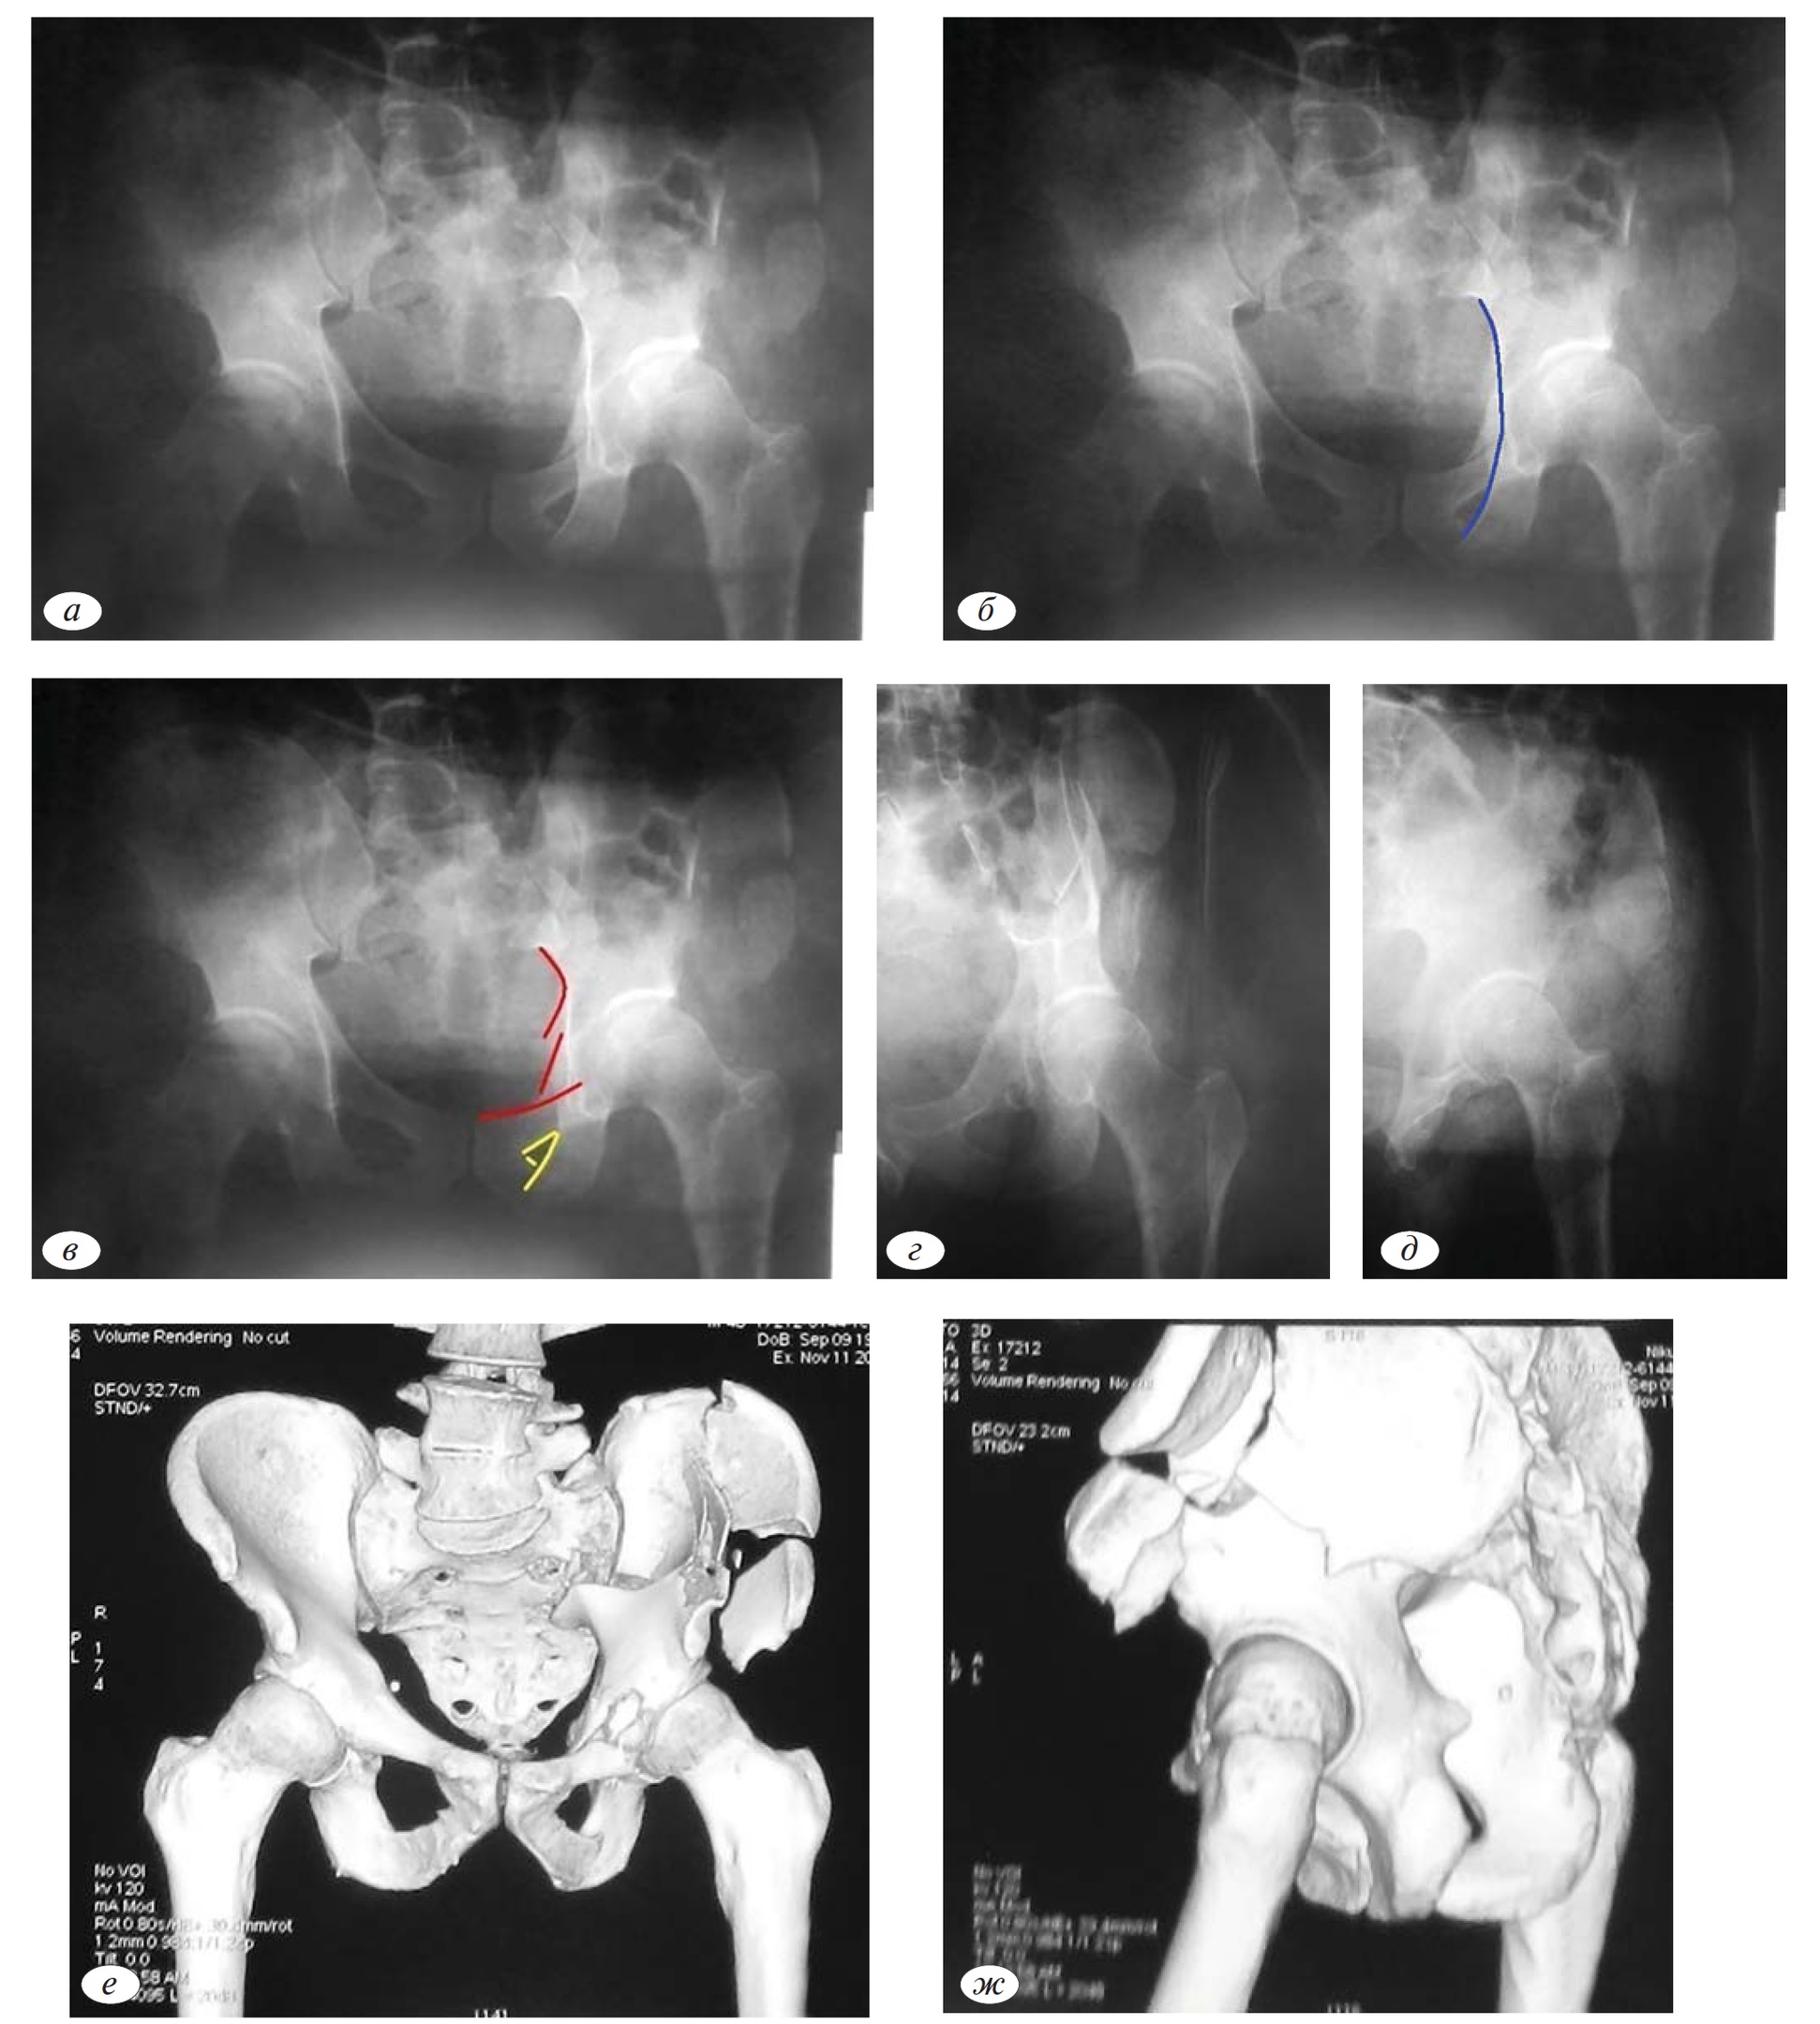

На обзорной рентгенограмме в следующем клиническом примере определяем целостность подвздошно-седалищной линии (рис. 3, а). Сохранение целостности этой структуры позволяет исключить переломы, при которых плоскость излома проходит через заднюю колонну. К этим переломам относят: перелом задней колонны, поперечный перелом, перелом задней колонны, ассоциированный с переломом задней стенки, поперечный перелом, ассоциированный с переломом задней стенки, Т-образный перелом, перелом передней колонны, ассоциированный с задним полупоперечным, двухколонный перелом (рис. 3, б).

Рис. 3.а — обзорная рентгенография таза при поступлении; б — первый этап определения атипичного внесуставного перелома передней колонны; в — второй этап определения атипичного внесуставного перелома передней колонны; г, д, е, ж — верификация внесуставного перелома передней колонны с помощью прицельных рентгенограмм в косой-подвздошной и косой-запирательной проекциях и компьютерной томографии.

Рис. 4.а, б — перелом вертлужной впадины слева; Ц — оскольчатый характер перелома задней стенки вертлужной впадины.

Сочетание повреждения подвздошно-гребешковой линии и контуров запирательного отверстия позволяет исключить перелом задней стенки, т.к. при подобных переломах сохраняется целостность обеих линий. Так же возможно исключить перелом передней стенки, при котором имеет место повреждение только подвздошно-гребешковой линии без повреждения контуров запирательного отверстия (рис. 3, в). Таким образом, методом исключения диагностирован перелом передней колонны.

Однако при наличии признаков перелома передней колонны, отсутствует повреждение суставной поверхности, что возможно подтвердить с помощью поли проекционной рентгенографии и компьютерной томографии. При анализе прицельных снимков видно, что линии перелома не проходят через суставную поверхность, что так же подтверждается на трехмерной компьютерной реконструкции костей таза (рис. 3, в—ж).

Исходя из результатов трехмерной реконструкции, наиболее подходящим диагноз можно сформулировать, используя классификации Л.Г. Школьникова (1966) или А.Ф. Лазарева (1992) [3, 4]. Согласно первой классификации этот перелом соответствует типу 3.В.б), т.е. перелом с нарушением непрерывности тазового кольца, как в переднем, так и заднем отделах.

Согласно второй классификации этот перелом относится к полифокальным повреждениям таза с вовлечением передних и задних отделов.

Наличие нескольких линий перелома не всегда свидетельствует об ассоциированном характере перелома (по классификации Judet—Letournel). Локализация этих линий может быть в пределах одной плоскости, что свидетельствует об оскольчатом характере перелома. На рентгенограммах (рис. 4, а, б) представлен пример оскольчатого перелома задней стенки вертлужной впадины.

При видимом наличии нескольких линий перелома, отмечается целостность других референтных линий, что свидетельствует о локализации очага повреждения только задней стенки (рис. 4, в, г).